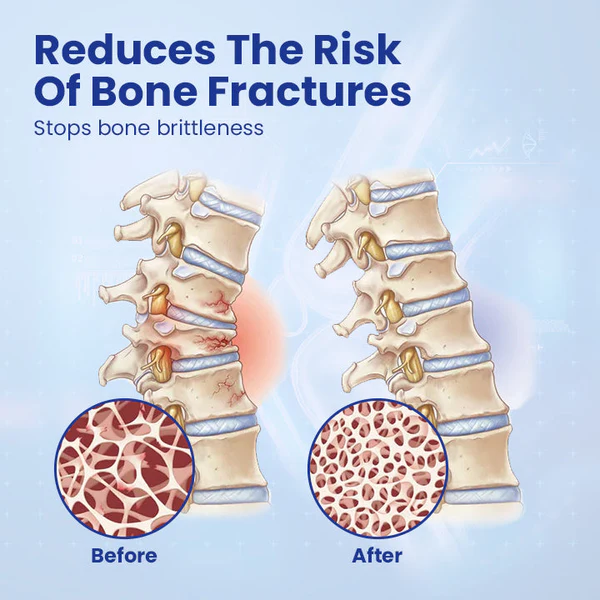

✓ Promotes overall bone health

✓ Reduces the risk of bone fractures